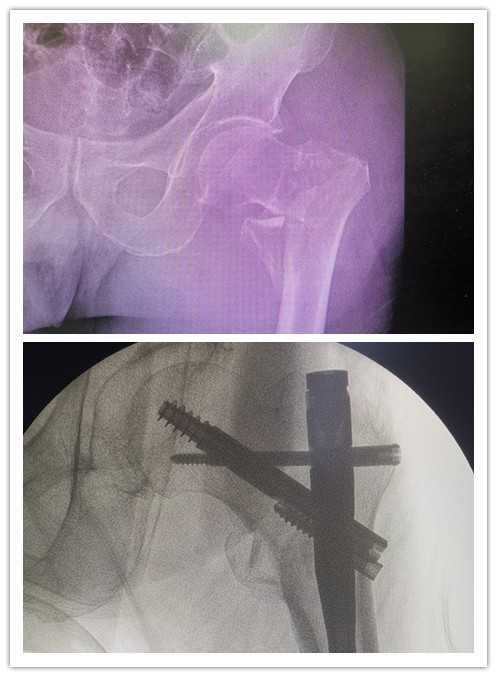

前不久,89歲的廖老因?yàn)樽呗窌r(shí)不小心摔傷左髖部,被緊急送到石化醫(yī)院。X線檢查顯示,廖老的左股骨轉(zhuǎn)子間粉碎性骨折。在完善相關(guān)輔助檢查后,骨科副主任醫(yī)師楊琲、錢(qián)立標(biāo)帶領(lǐng)團(tuán)隊(duì)認(rèn)真研究患者影像資料,考慮其基礎(chǔ)疾病較多,有高血壓、糖尿病以及重度骨質(zhì)疏松癥病史,再結(jié)合年齡、病情和康復(fù)鍛煉需要,召集多學(xué)科綜合會(huì)診評(píng)估風(fēng)險(xiǎn)。經(jīng)與患者和家屬積極溝通,最終決定運(yùn)用股骨髓內(nèi)釘系統(tǒng)PFBN,為廖老行股骨轉(zhuǎn)子間骨折閉合復(fù)位內(nèi)固定手術(shù)。

手術(shù)當(dāng)日,在麻醉科的協(xié)助下,骨科團(tuán)隊(duì)經(jīng)透視成功將廖老的左髖部牽引復(fù)位,用4個(gè)小切口順利置入PFBN固定,不到40分鐘就成功完成手術(shù)。